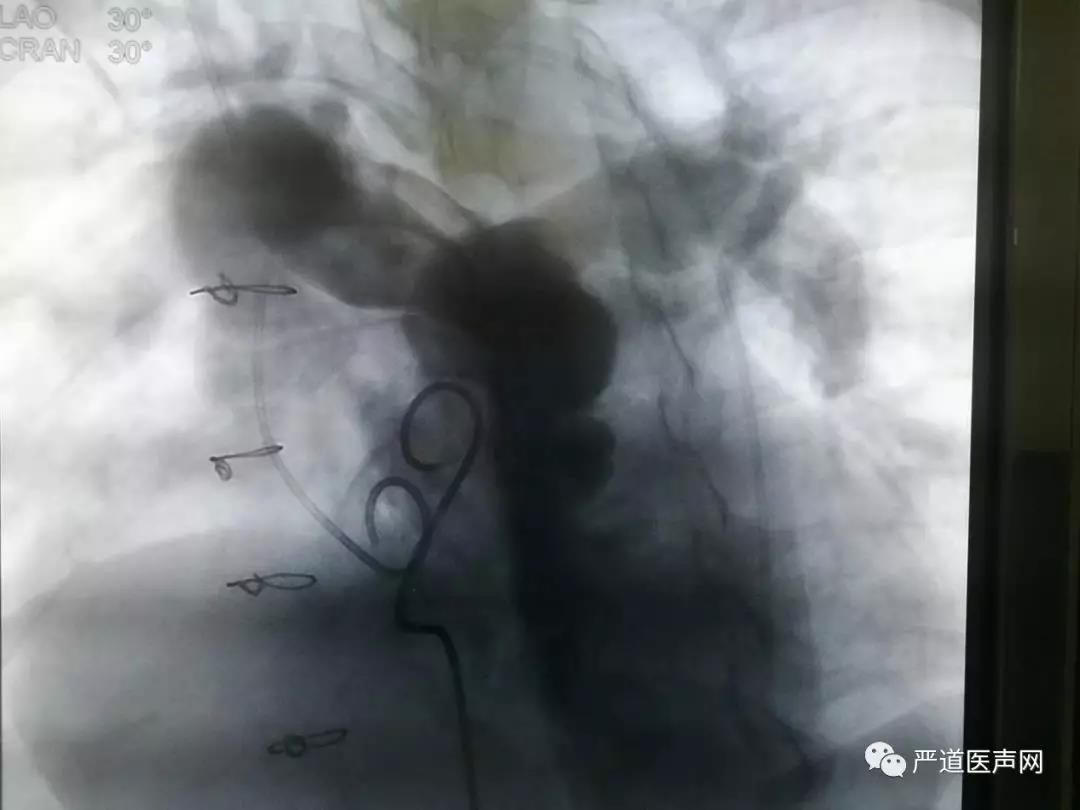

• 造影结果

肺动脉造影显示患者肺动脉主干增宽,左右肺动脉未见明显狭窄,肺动脉瓣大量返流。随后注入肝素5000U,选择AGA公司34mm球囊测量直径的同时行主动脉根部造影,结果提示患者冠脉显影良好,未受到压迫。

右股静脉交换加硬导丝,置换24FGore血管鞘,送入输送鞘管及30*25mm VENUS P带瓣支架,反复造影定位后释放瓣膜。再次造影确定瓣膜位置良好,冠脉显影良好,床旁超声检查显示支架瓣膜启闭正常,未见明显返流及瓣周漏,跨瓣压差仅6mmHg。